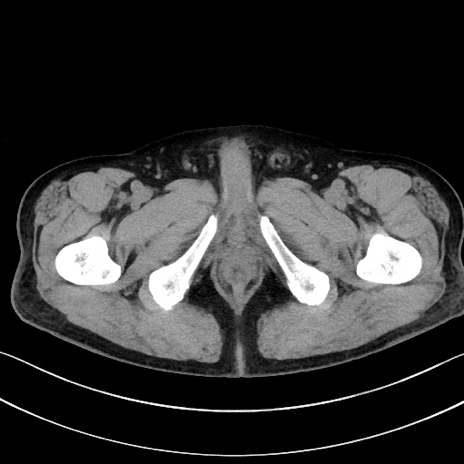

冠状断像

症例15(横断像)

【症例】70歳代男性

【主訴】腹痛

【現病歴】今朝から腹痛あり。全体的に痛い。特に左上の方。排ガスが今日はない。冷や汗が出る。

【既往歴】直腸癌術後

【身体所見】左側腹部〜上腹部に圧痛あり。腹膜刺激症状明らかなではない。軽度反跳痛。左下腹部に術後瘢痕あり。

【データ】WBC 7700、CRP 0.02